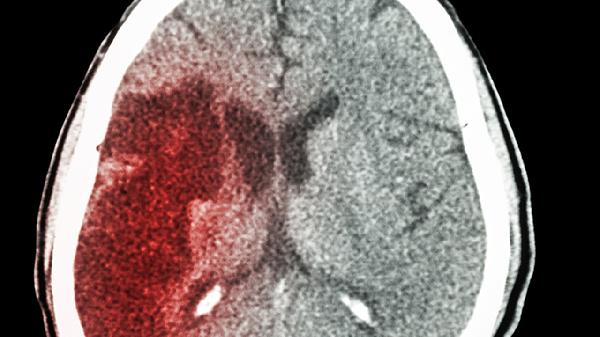

小脑出血能否治好取决于出血量、治疗时机及并发症情况,多数患者经过及时治疗可改善症状,部分重症可能遗留功能障碍。

小脑出血的治疗效果与出血量密切相关。出血量小于3毫升且未压迫脑干时,通过绝对卧床、控制血压及脱水降颅压治疗,症状可能在1-2周内缓解。常用药物包括甘露醇注射液、呋塞米注射液等降低颅内压,同时需使用乌拉地尔注射液等控制血压。若出血量在3-10毫升之间,可能出现头痛、呕吐、共济失调等症状,此时需在药物治疗基础上密切观察,必要时进行外科干预。对于出血量超过10毫升或出现脑疝征兆者,需紧急行后颅窝减压术或血肿清除术,术后可能需结合康复训练改善平衡功能。

部分患者因出血位置特殊或合并脑室铸型,即使手术也可能遗留持续性眩晕或步态不稳。高龄、基础疾病多的患者恢复周期较长,可能需3-6个月康复训练。少数出血累及脑干生命中枢者预后较差,可能危及生命。早期康复介入对运动功能恢复有帮助,包括前庭康复训练、平衡板训练等物理治疗手段。

患者应严格遵医嘱控制高血压等基础病,避免剧烈活动或情绪激动。恢复期需在康复师指导下进行步态训练,饮食以低盐低脂为主,定期复查头颅CT监测恢复情况。若出现头痛加重或意识改变需立即就医。